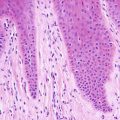

3.3.2 Histology

Histologic changes consist of a non-inflammatory subcorneal blister at the level of the granular layer (Fig. 3.7). In many cases, the stratum corneum, which is the blister roof, is desquamated and not present in the biopsy specimen. Its absence is often overlooked, making the diagnosis difficult. Rare acantholytic cells may be observed within the granular layer (Fig. 3.8). There is virtually no underlying inflammation within the dermis. Special stains for bacteria are negative [15].

Fig. 3.7

Staphylococcal scalded skin syndrome features a subcorneal blister in the absence of any inflammatory infiltrate